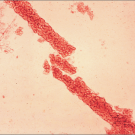

Pellagra

Julie Joseph, MD; Andy McWilliams, MD; Kamalkumar Kolappa, MD; Andrew Buzan, MD

<p><img alt="" src="/sites/default/files/images/Pellagra.jpg" style="height:81px; margin-left:8px; margin-right:8px; width:150px; float:left" />For 4 months, a...